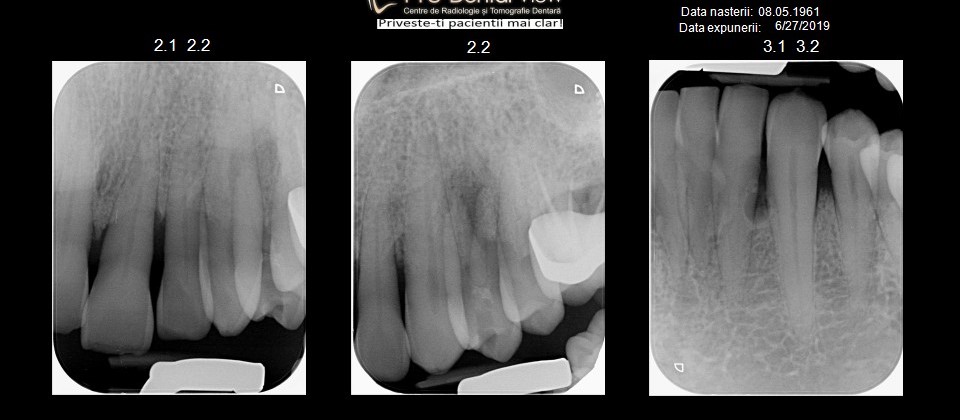

Atașez pozele unui pacient care până la vârsta de 44 ani nu a fost niciodată la dentist, cu reflex de vomă exagerat și igienă deficitară, speriat că i s-a propus extracția a peste 50% din dinți din cauza mobilității generalizate de gradul II și III. Am mers pe varianta clasică, debridare parodontală nechirurgicală, la microscop, cu anestezie locala în toate cadranele, realizată într-o singură ședință. Am administrat antibiotic pe cale generală și am urmărit respectarea indicațiilor de igienă prin controale lunare. Rezultatele la 6 luni vorbesc de la sine, acum putând să ne ocupam liniștiți de regenerarea defectelor osoase de la nivelul 21 22, de altfel singurii dinți care mai au mobilitate.

Iar retracția de la 31 s-a vindecat singură 🙂 Pentru că timpul e, uneori, cel mai bun tratament.